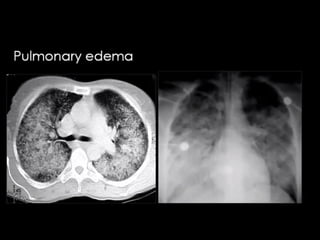

-Pulmonary oedema is a broad descriptive term and is usually

defined as an abnormal accumulation of fluid in the extra-vascular

compartments of the lung 1

.

-HRCT findings in cardiogenic pulmonary edema

Bilateral septal thickening and ground-glass opacity.

Perihilar and gravitational distribution predominatly in the

dependent lung.

Cardiomegaly and pleural fluid.